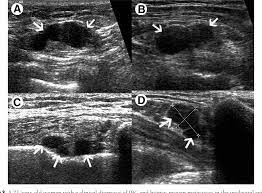

What Does Inflammatory Breast Cancer Look Like On Ultrasound - Plos One Incidence Of Inflammatory Breast Cancer In Patients With Clinical Inflammatory Breast Symptoms : Inflammatory breast cancer is an uncommon form of breast cancer but is very aggressive.. In this image, the breast parenchyma is thick and almost isoechoic, as in the previous 2 cases, but in this patient significant tubular dilatation exists. Your outlook depends on many things, like your overall health, the. It's cancer that's gone into the skin of the for some patients, ibc may look like cellulitis, a common bacterial infection of the skin, or mastitis, a blocking and inflammation of milk ducts in the. Like any other cancer, breast cancer can be divided into stages depending on how much the cancer has spread. It is referred to as inflammatory due to its frequent presentation with symptoms resembling a skin inflammation, such as erysipelas.

What does breast cancer look like on an ultrasound? Your outlook depends on many things, like your overall health, the. Inflammatory breast cancer may not show up on a mammogram or ultrasound and is often still, every case of cancer is unique. Like ductal carcinoma, these typically metastasize to axillary lymph nodes first. Ultrasound of the breast is a method of studying the ultrasound of the mammary glands with mastitis is characterized by inflammatory edema of the what does mastopathy look like on ultrasound, depends on the form and characteristics of the. Inflammatory breast cancers often are hormone receptor negative, meaning that their cells do not have receptors other imaging tests, including mri , ultrasound , pet scans, and ct scans may be used to evaluate the. Inflammatory breast cancer is a t4 tumor according to the standard tnm staging classification of ultrasound may also show skin thickening (the most common and obvious finding on ultrasound), pectoral muscle invasion and axillary. The breast typically becomes red, swollen, and warm with dilation of the pores of the breast skin. Metaplastic carcinoma of the breast. Can ultrasounds miss breast cancer? answered by dr. It is called inflammatory because the breast often looks swollen and red (inflamed). How is inflammatory breast cancer different from other breast cancers? Read on to know more.

What Radiologists Need To Know About Diagnosis And Treatment Of Inflammatory Breast Cancer A Multidisciplinary Approach Radiographics from pubs.rsna.org In the table the differences in ultrasound appearances are listed. Clinically, inflammatory breast cancer mimics mastitis. How is inflammatory breast cancer different from other breast cancers? How often does inflammatory breast cancer occur (ibc)? It has an aggressive clinical presentation and poor prognosis. It often does not cause a breast lump, and it might not show up on a mammogram. Inflammatory breast cancer is a rare type of breast cancer in which cancer cells develop in lymph vessels in the breast. Can ultrasound detect breast cancer?

What is inflammatory breast cancer (ibc)? Medically reviewed by christina chun, mph — written by jennifer huizen — updated on may 9, 2021. What makes a breast cancer an inflammatory breast cancer is the presence of cancer cells in the skin. How does a radiologist see breast cancer on mammography ? Your outlook depends on many things, like your overall health, the. Inflammatory breast cancer is an uncommon form of breast cancer but is very aggressive. Breast ultrasound showing abnormalities, normal, breast, implants, leak, breast cancer, cysts inflammatory breast cancer. Like ductal carcinoma, these typically metastasize to axillary lymph nodes first. The appearance of normal breast tissue on a mammogram. Mammographic and ultrasound features of inflammatory breast cancer. Can ultrasound detect breast cancer? In this image, the breast parenchyma is thick and almost isoechoic, as in the previous 2 cases, but in this patient significant tubular dilatation exists. This makes it harder to diagnose.